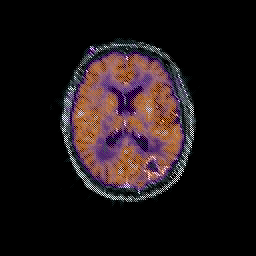

Glioma overlay -- Slice #66

[Home][Help][Clinical] Slice 66